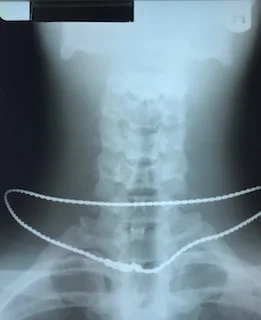

After Corrective Care (manual short term adjusting)